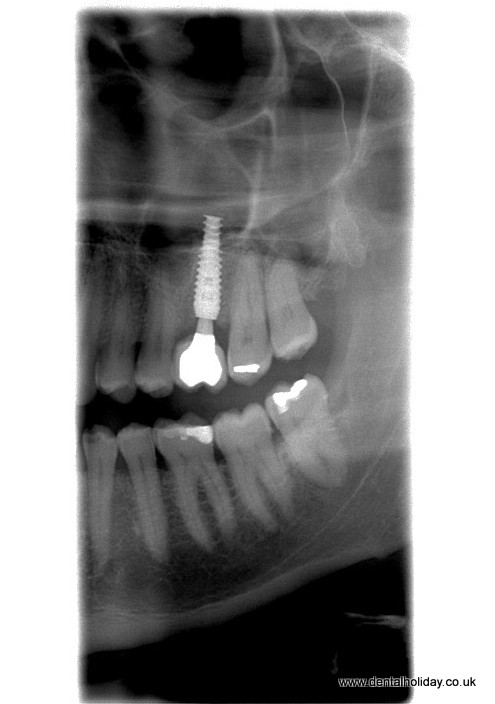

Smile Clinic provides dental expertise under one roof, giving our patients the best in dental technology with our implantologist expert, Dr. Marek (Mark) Salka performing the surgery in an efficient and effective manner.

Our recent patient, Charles, a Londoner, finally found the time to come to Smile Clinic – Dental Holiday for implant treatment. He turned it into a real holiday with his wife and a couple of friends, enjoying the spa town of Piešťany, where one of our clinics is located.